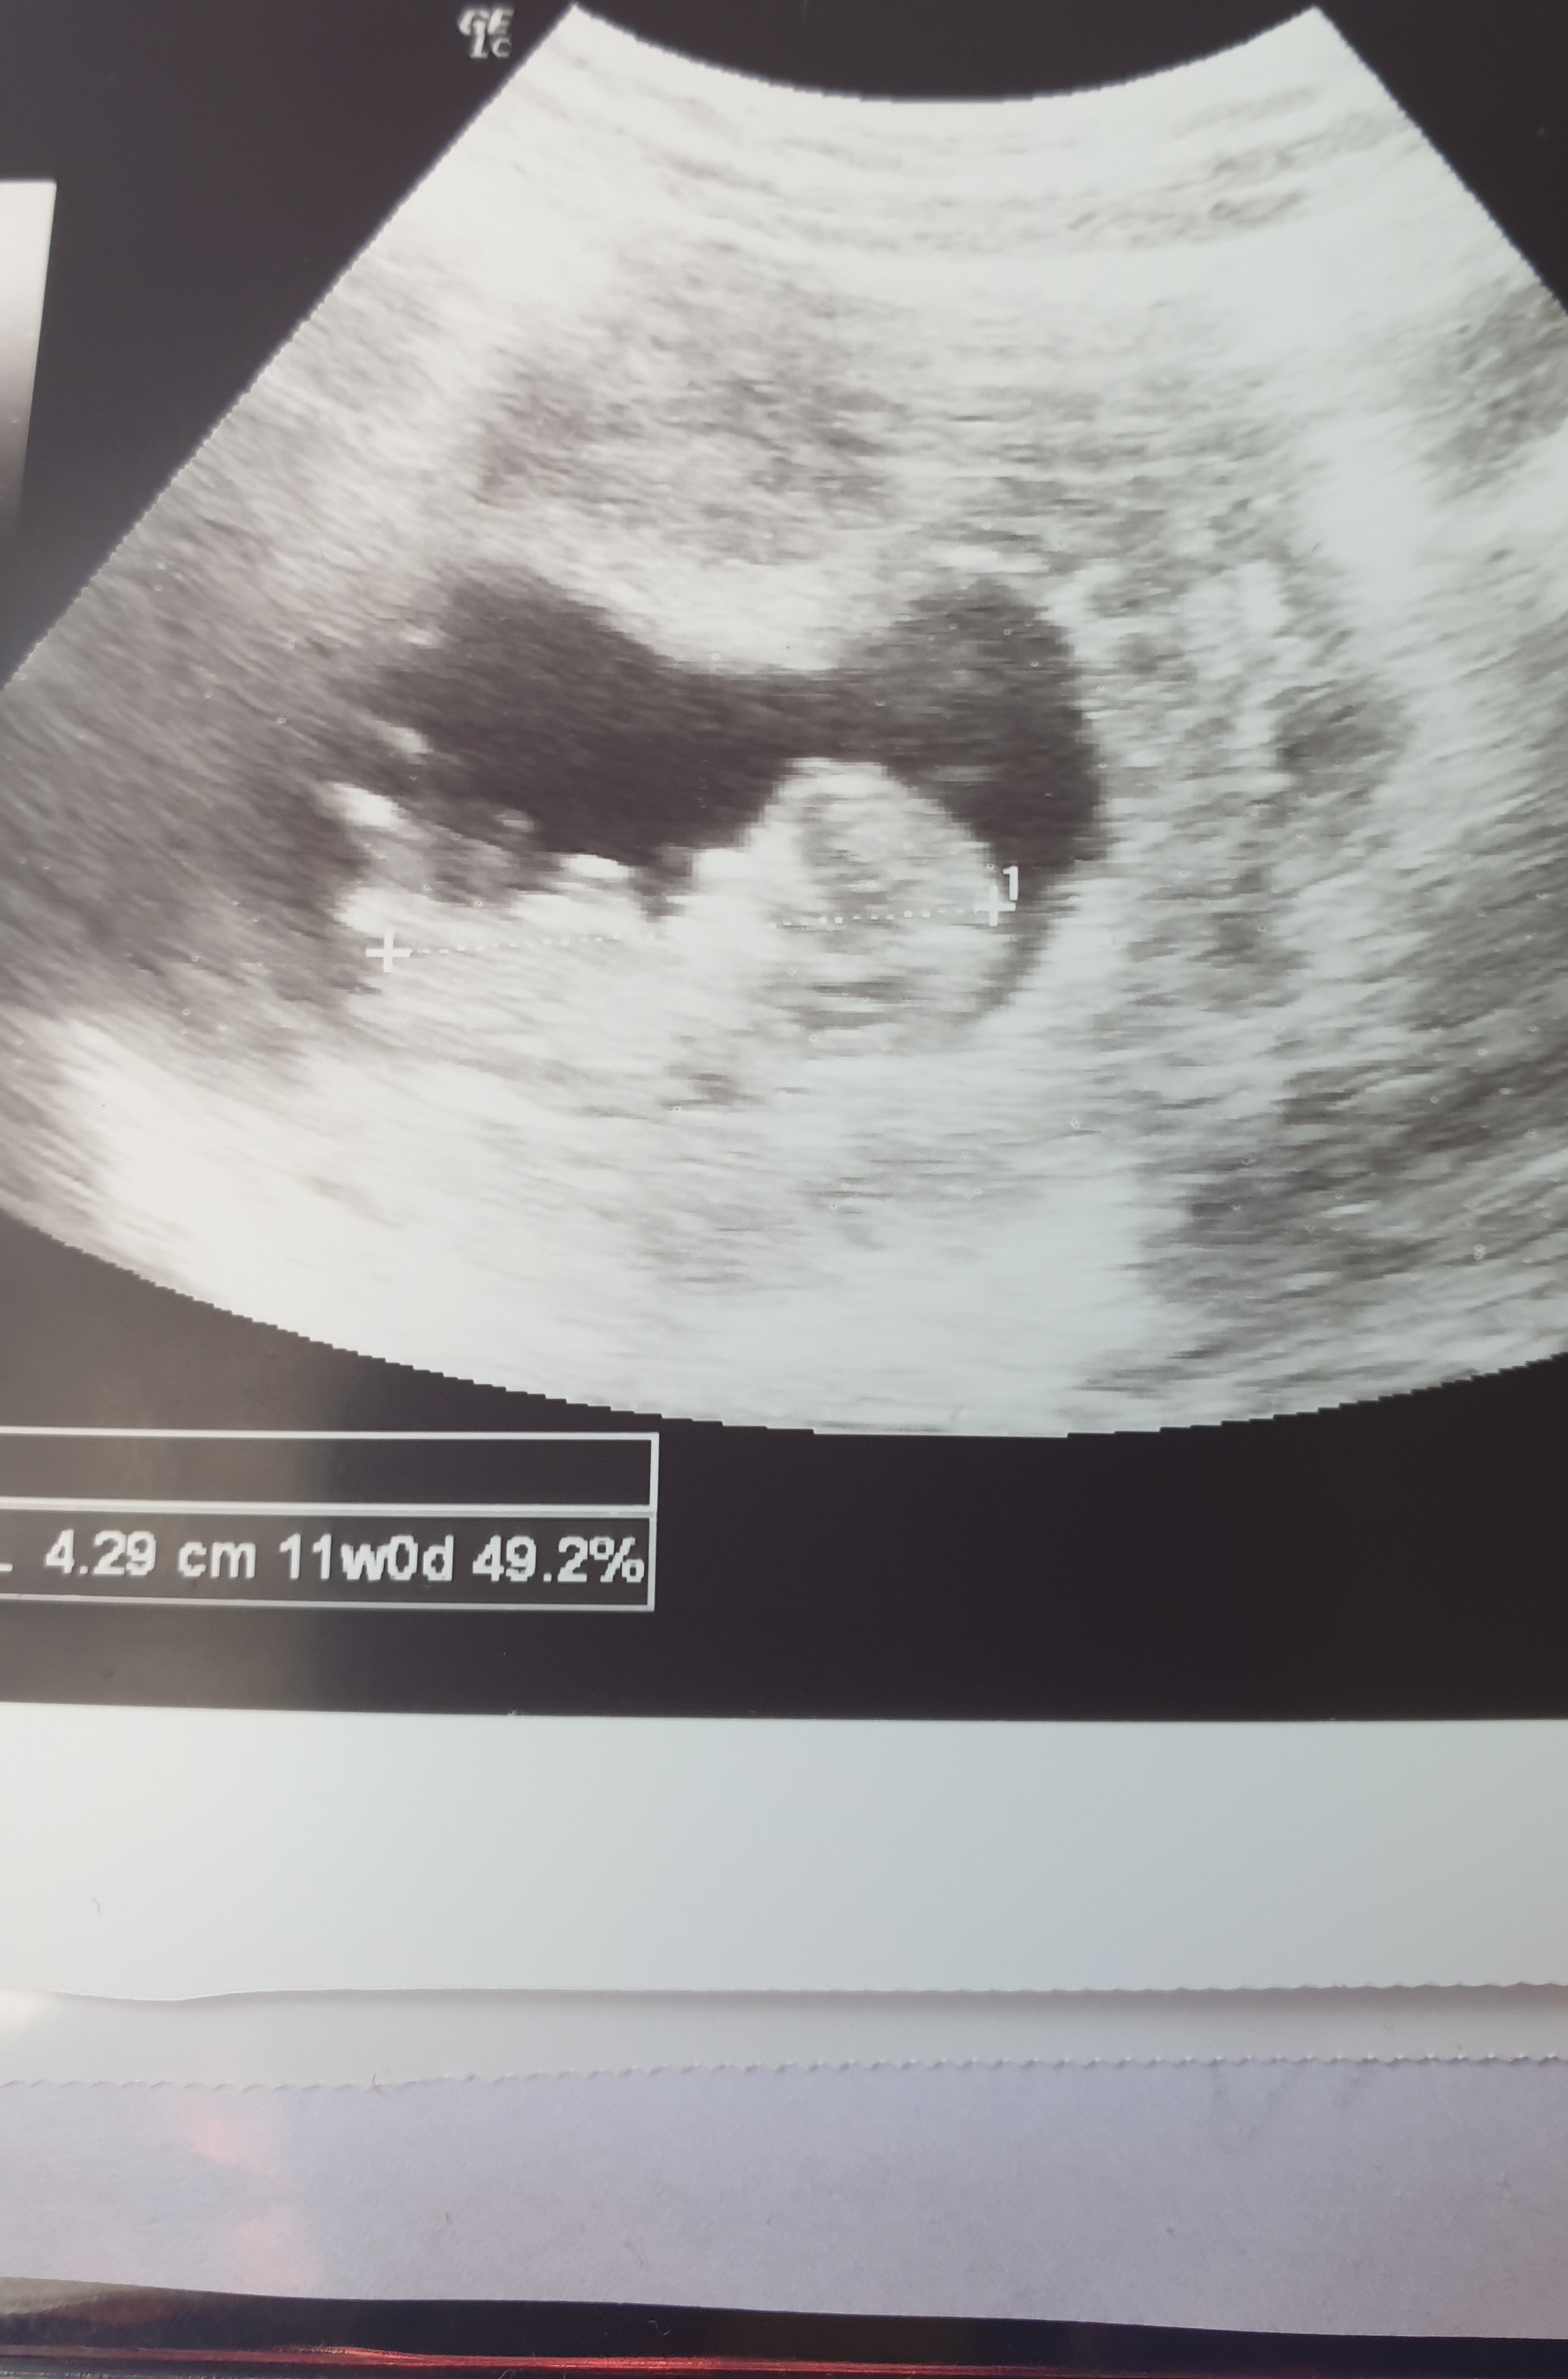

Dziewczyny! Przedstawiam Wam moją 4cm czupakabrę 🥰😍❤ 11tydzien, za 2 tyg prenatalne mam 😊

Patrzcie jaki ma piękny nos moje dziecko 🤣 lekarz aż się zaśmial, mowi, ze piekna kosc nosowa 😁